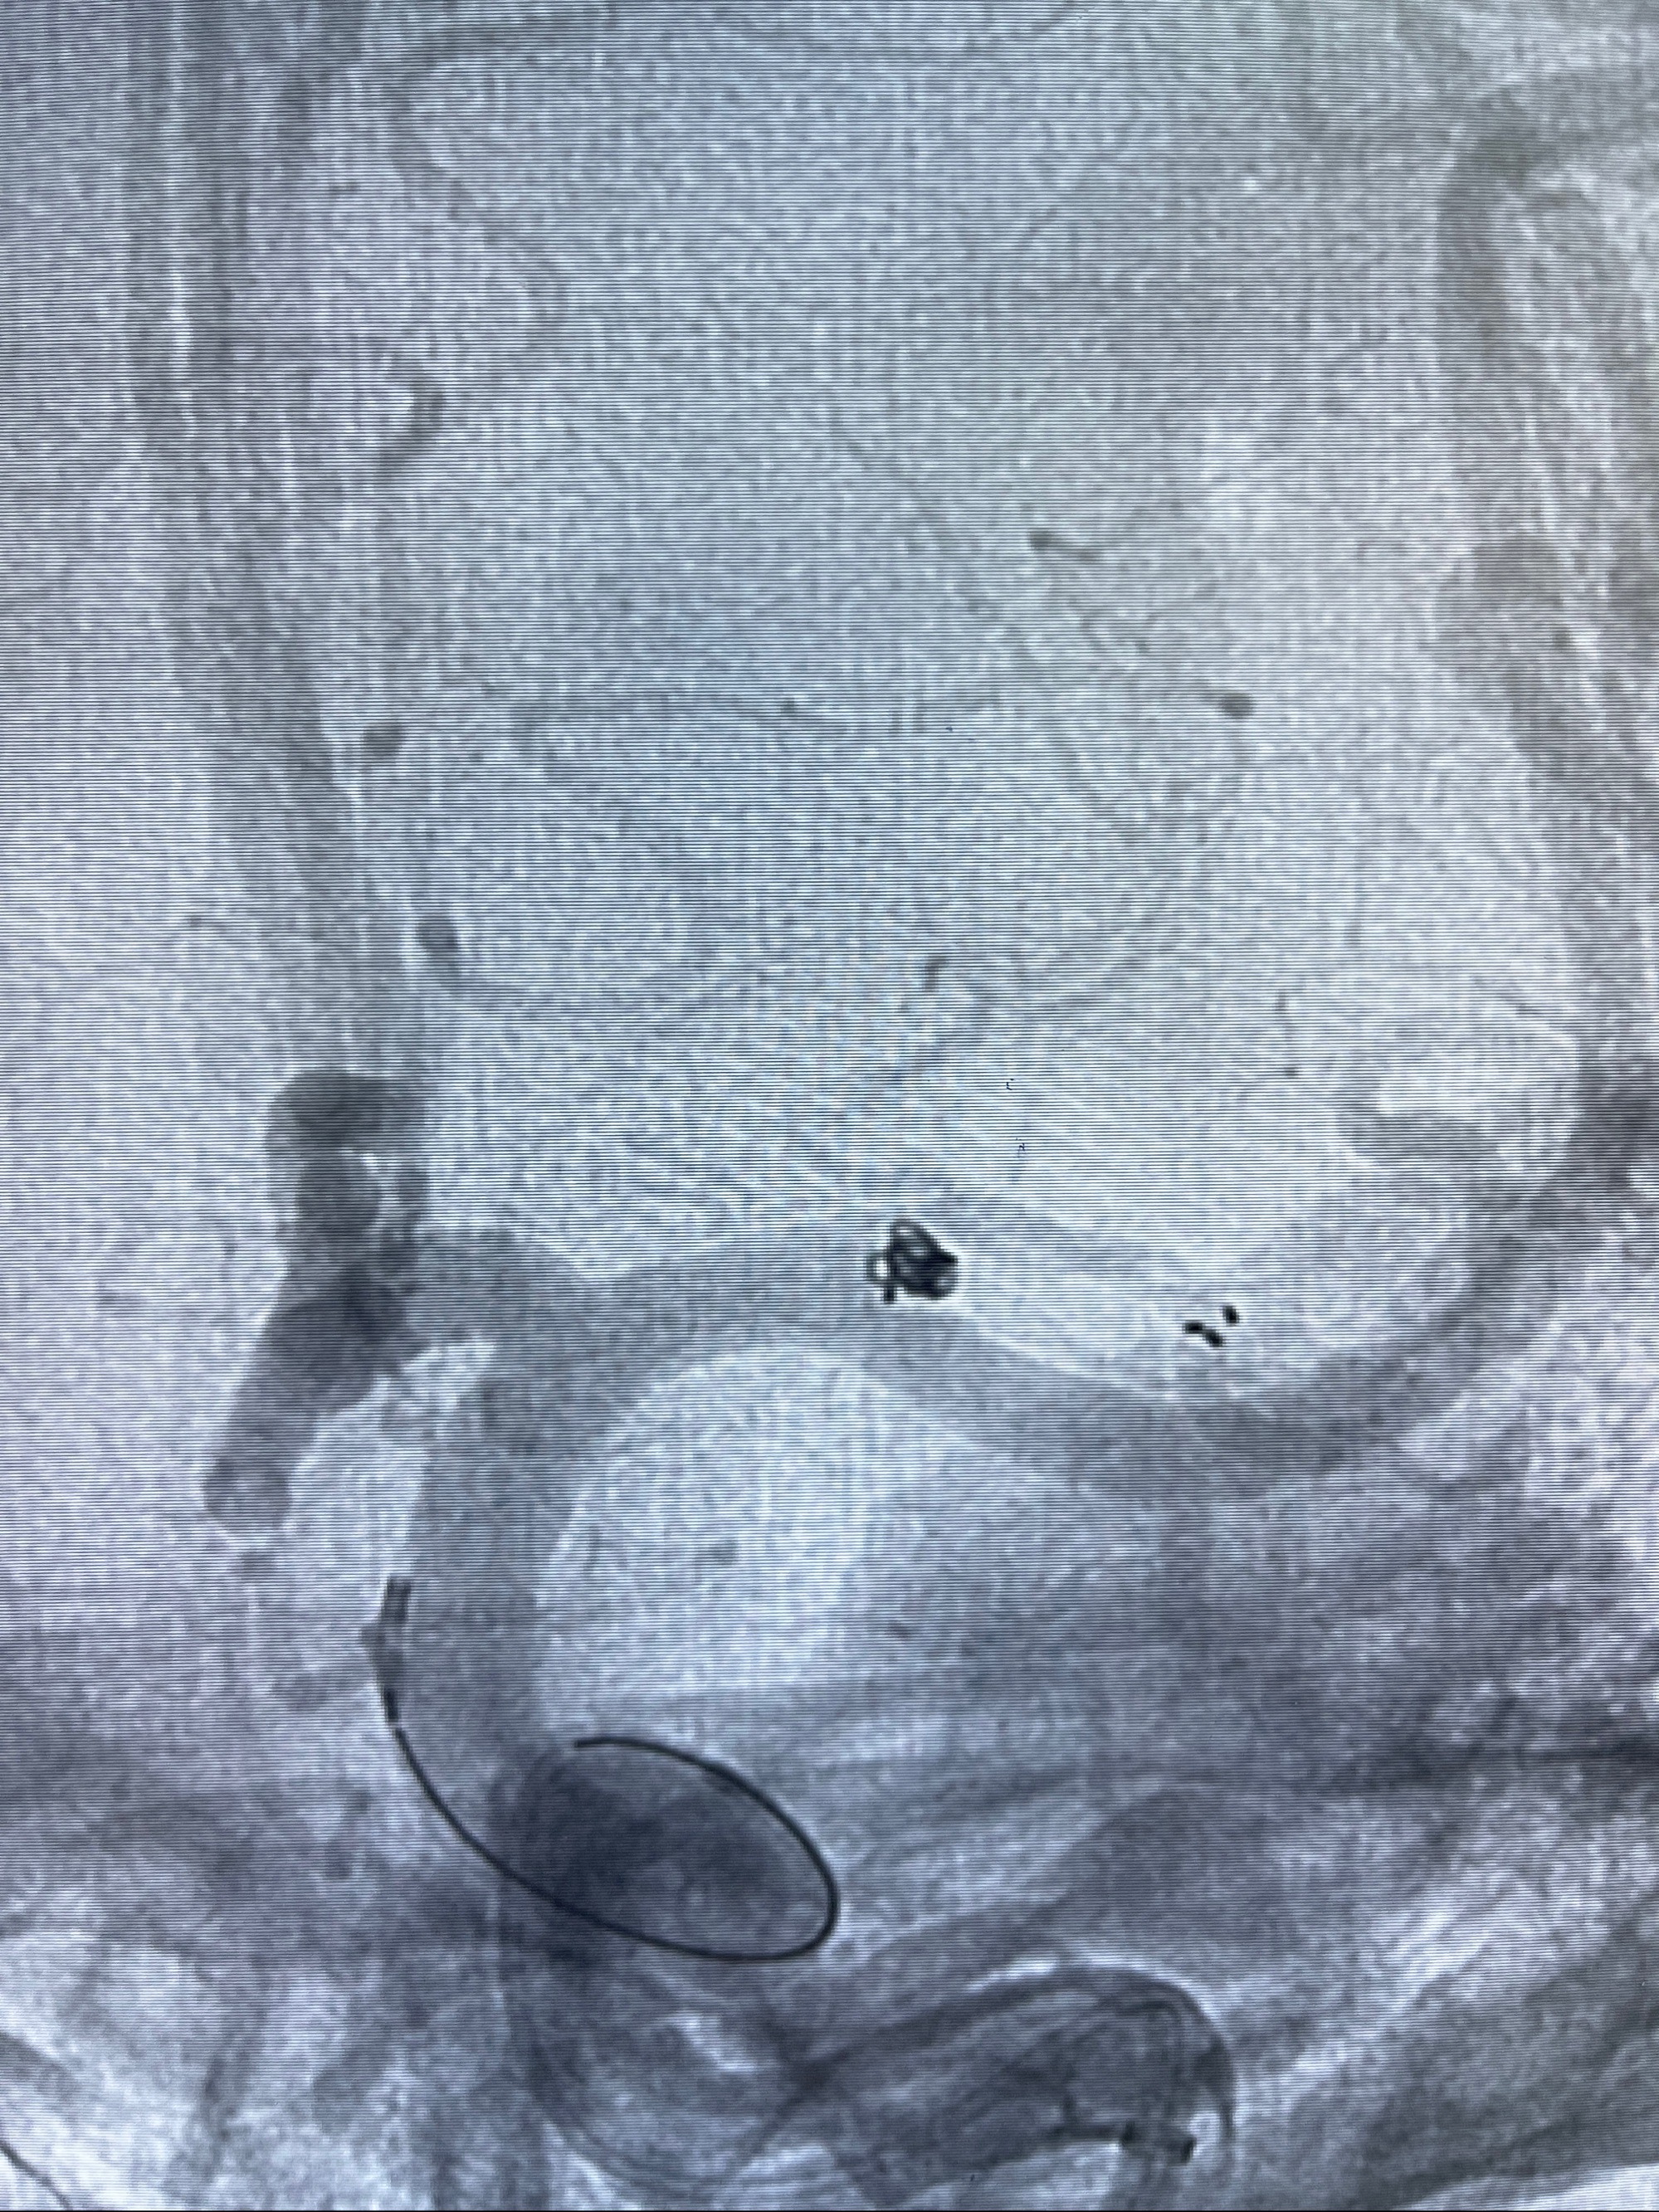

2.外科手术夹闭or介入支架辅助栓塞

麻醉苏醒佳,遵嘱动作